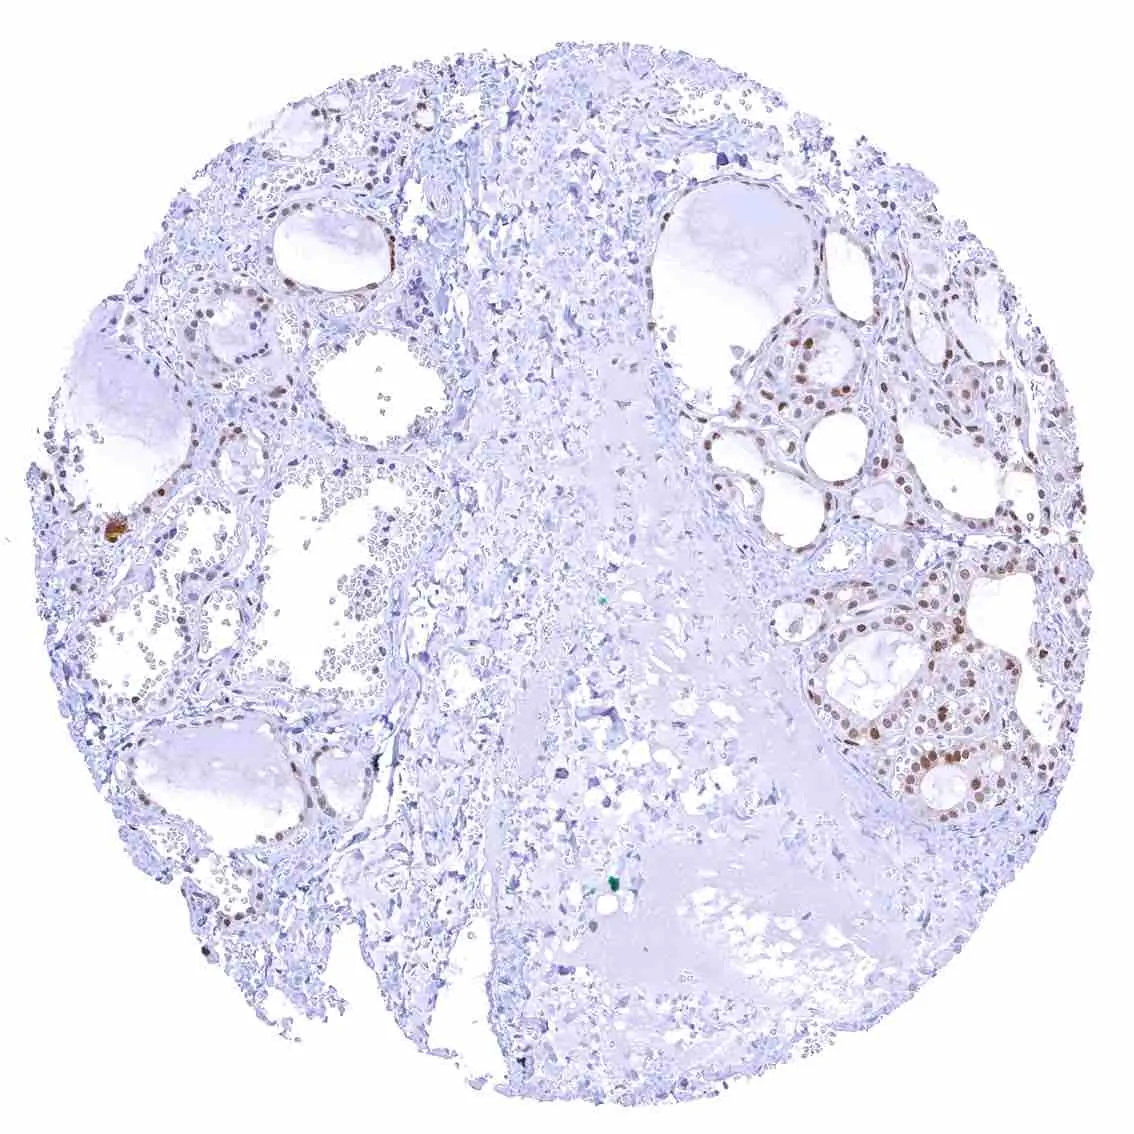

Thyroid gland – Weak to moderate nuclear p27 positivity of most follicular cells.